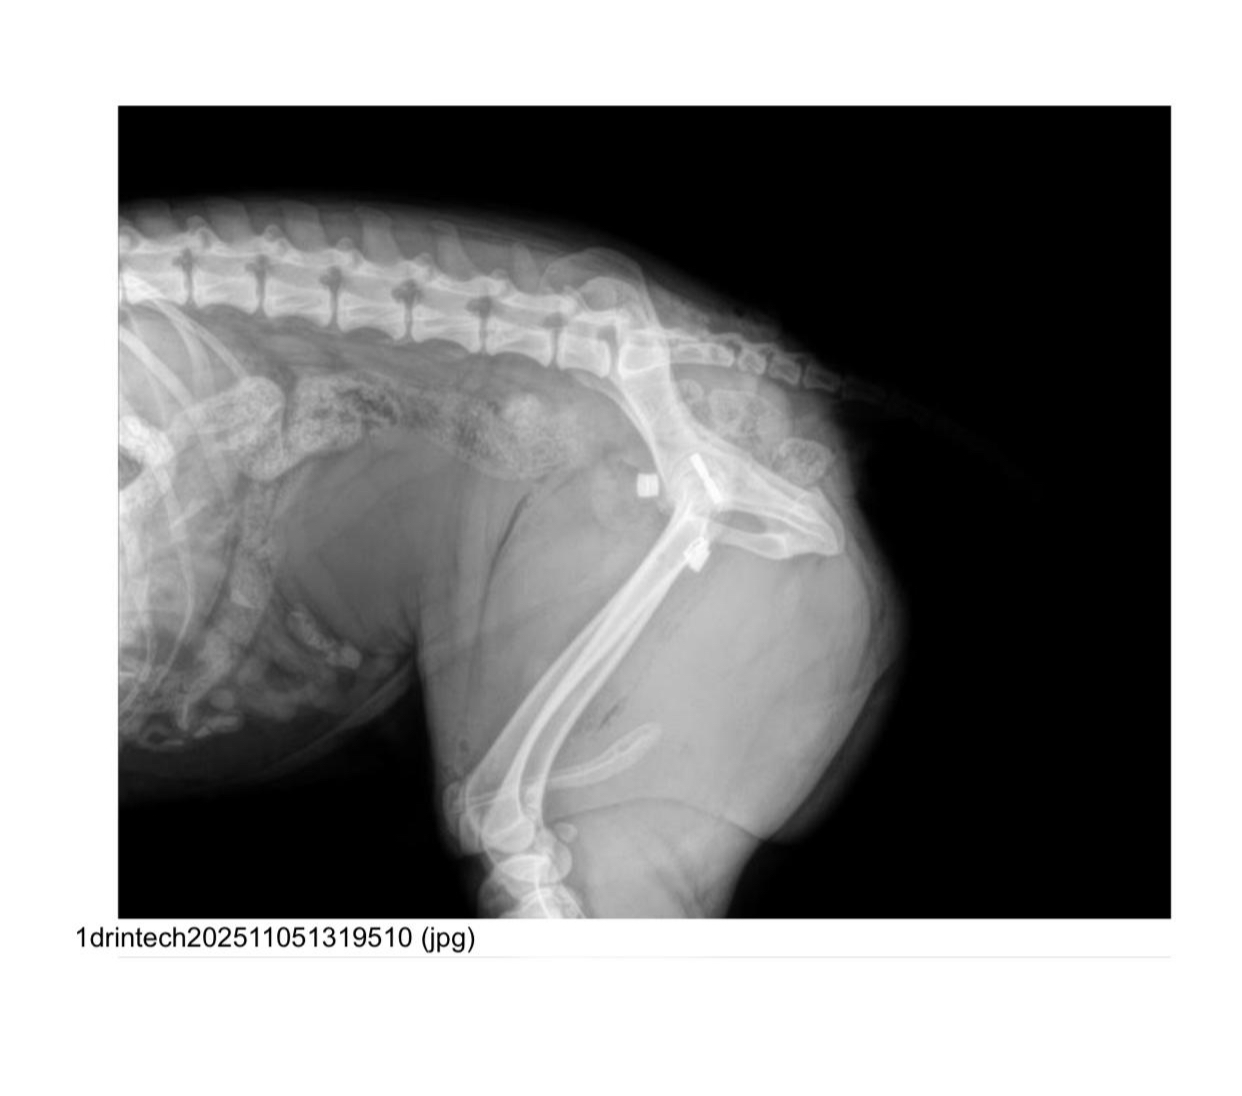

Born: 2024 – Breed: Podenco mix – Male

weighs 19 kilos.

He’s a good boy who recently came to live with us after being hit by a car, which dislocated his hip. He’s currently recovering well from surgery. Son is very easy to handle and lets us treat him; he even licks your hands while you do it. He’s a trusting dog who readily accepts your requests. He walks well on a leash and is very attentive to anything you ask of him. He gets along well with other dogs, both male and female, large and small, and we’re sure he’ll start playing with them soon. Although he’s a young Podenco, he has a very calm energy and has rested without any problems after surgery. We believe he’s a good boy who deserves a family to play and go for walks with. Despite his hip injury, he can live a normal life, going on hikes and doing anything his new family wants him to do.